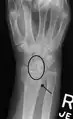

X-ray images indicate scapholunate ligament instability when the scapholunate distance is more than 3 mm, which is called scapholunate dissociation.[7] A static scapholunate instability is generally readily visible, but a dynamic scapholunate instability can only be seen radiographically in certain wrist positions or under certain loading conditions, such as when clenching the wrist, or loading the wrist in ulnar deviation.[6]

Dynamic instability: Increased scapholunate distance (between yellow lines) upon ulnar deviation of the wrist, but not otherwise.